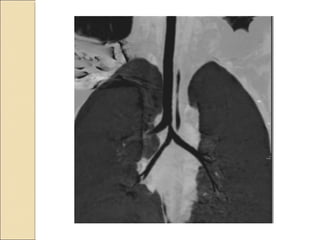

A resident in radiology presents two interesting cases: the first involves a harmatoma, and the second concerns a patient with double superior vena cava and tracheal bronchus. Both cases provide learning opportunities for radiology residents to recognize rare anatomical variations and abnormalities.